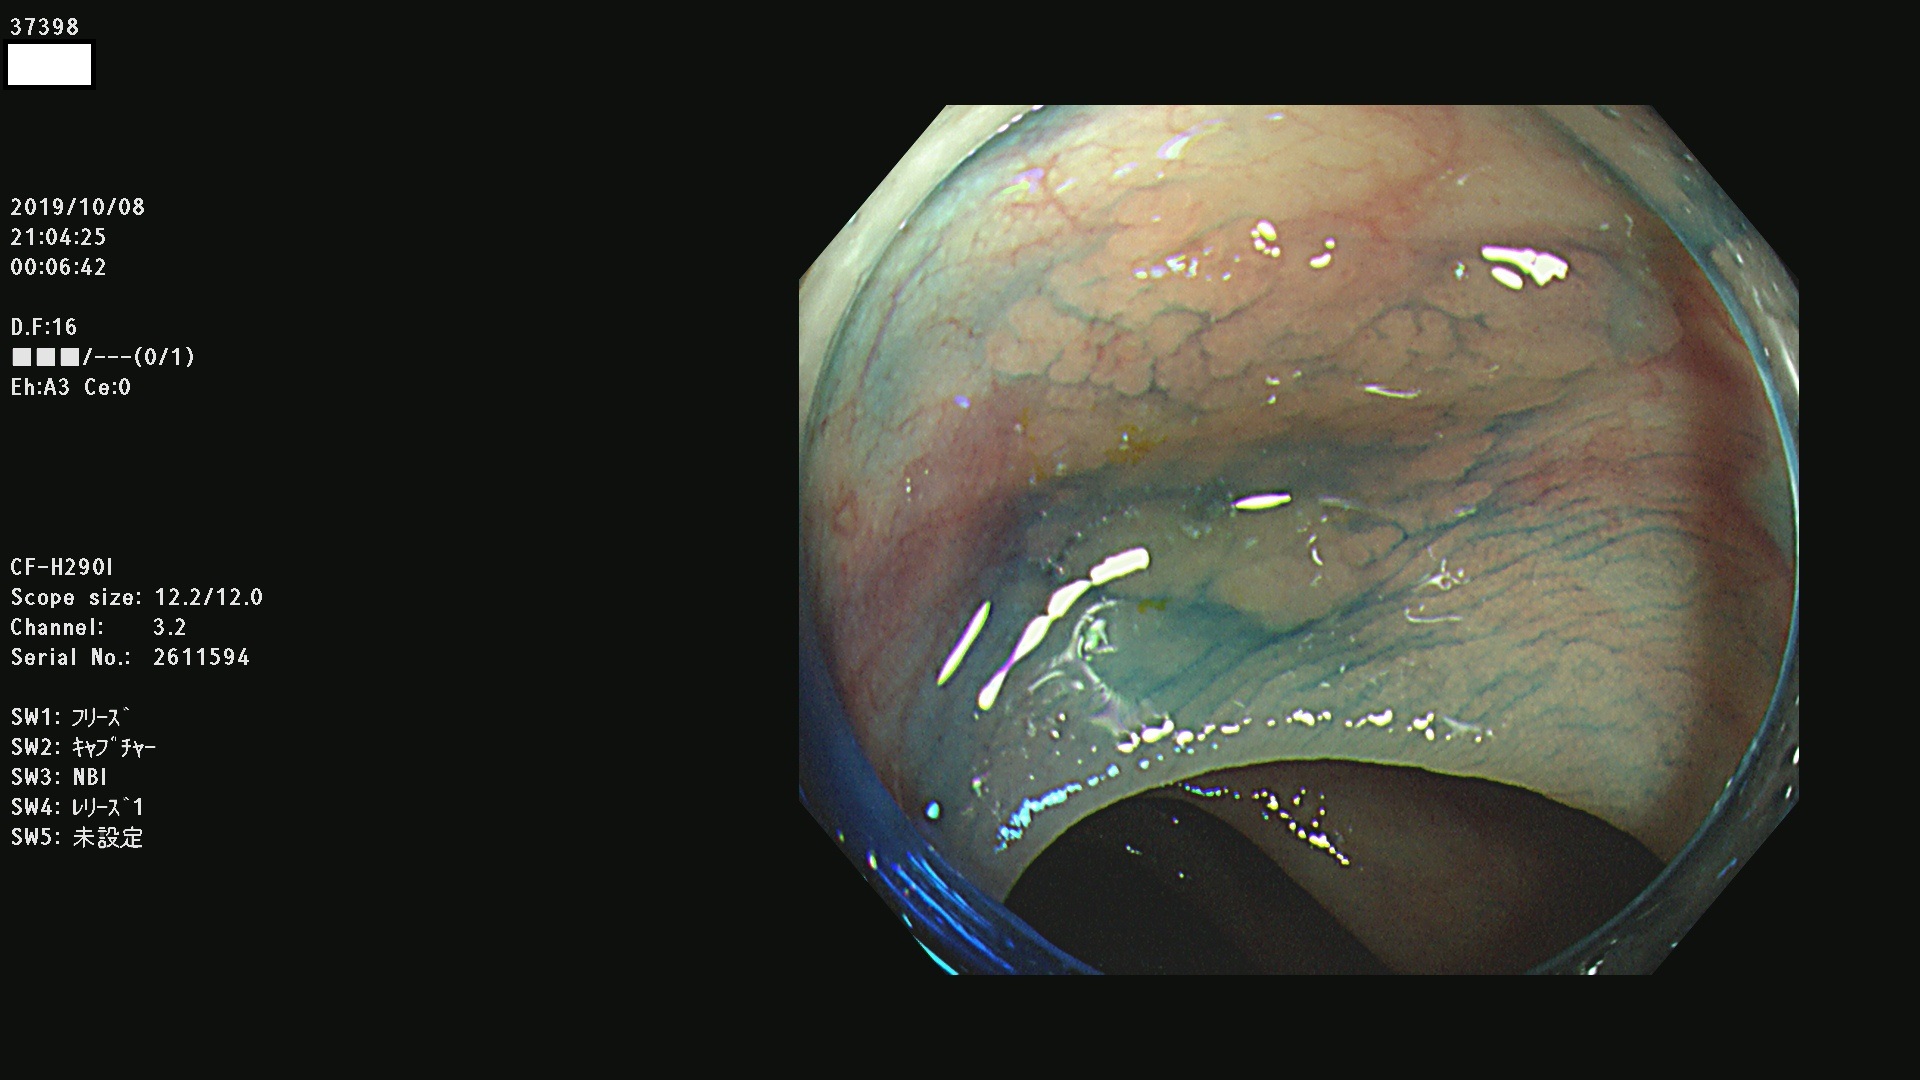

37300(SSAPのみ) 37301 37303 37304 37306 37307 37308 37309 37312 37313 37315(SSAPのみ) 37316 37317(SSAPのみ) 37319 37321(SSAPのみ) 37322 37323 37324 37325 37326 37328(SSAPのみ) 37329 37330 37331 37332(SSAPのみ) 37333 37334 37336 37337 37338 37340 37342 37343(SSAPのみ) 37344 37345 37346 37347 37348 37352(SSAPのみ) 37353 37354 37355 37356 37358 37360 37361(SSAPのみ) 37362 37363 37366 37367 37369 37370 37371 37372(SSAPのみ) 37375 37376 37377 37380 37381(SSAPのみ) 37382 37383 37384 37385(SSAPのみ) 37386 37387 37388 37389 37390 37392(SSAPのみ) 37393 37394 37395 37396(SSAPのみ) 37397 37398(SSAPのみ) 37399

発見困難で危険性の高い平坦型病変(上記100名より抽出) )